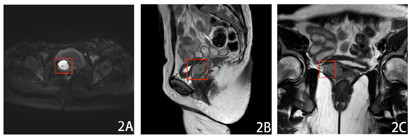

⑴宫颈癌术后:下腹呈术后改变,子宫术后缺如,阴道残端一软组织肿块,伴代谢增高,倾向肿瘤复发。腹膜后、双侧腹股沟多个淋巴结显示,未伴代谢增高,倾向增生性可能;⑵双侧额扁桃体、舌扁桃体炎症。双侧颈部多个淋巴结显示,部分伴代谢增高,倾向良性;⑶前纵膈片状等低密度影,伴代谢轻度增高,倾向胸腺显示。左侧乳腺上象限一钙化灶;⑷升结肠、乙状结肠、直肠见条片状代谢增高影,CT未见明显占位性病变,倾向炎性可能;⑸脊柱多个椎体退行性改变;右侧耻骨见一低密度影,未伴代谢增高,倾向良性;中轴骨及四肢骨髓腔代谢增高,倾向反应性改变(图1)。

患者,女性,38岁,已婚,孕7产2。主诉"宫颈癌"术后13个月,发现阴道残端复发9 d。患者2020年1月因"同房后阴道流血1个月余"就诊于省内某三甲医院,行妇科检查见子宫颈约1.5 cm×1 cm结节样肿瘤,无接触性出血,行阴道镜检查+宫颈活检,病理提示宫颈恶性肿瘤,考虑腺癌。完善相关术前检查后于2020年1月17日在该院行"腹腔镜下广泛全子宫切除+双侧输卵管切除+盆腔淋巴结清扫+双侧卵巢移位+盆腔粘连松解术"。术后病理提示:宫颈恶性肿瘤,结合免疫组化考虑腺癌,部分伴神经内分泌癌,浸润<1/2肌层;(双侧宫旁、颈体交界、阴道壁残端)未见癌;宫腔分泌反应子宫内膜伴息肉;子宫多发性平滑肌瘤;双侧输卵管慢性炎症;淋巴结未见癌转移。手术病理分期:宫颈低分化腺癌伴神经内分泌癌IB1期,术后未行辅助放化疗。患者出院后定期复查,2021年3月6日当地医院超声检查提示阴道残端软组织肿块,遂至我院完善全身正电子发射计算机断层显像/计算机断层显像(positron emission tomography-computed tomography,PET-CT)检查,结果提示"宫颈癌术后":下腹呈术后改变,子宫术后缺如,阴道残端一软组织肿块,伴代谢增高,倾向肿瘤复发。腹膜后、双侧腹股沟多个淋巴结显示,未伴代谢增高,倾向增生性可能。考虑患者"宫颈癌术后复发"收入我院。